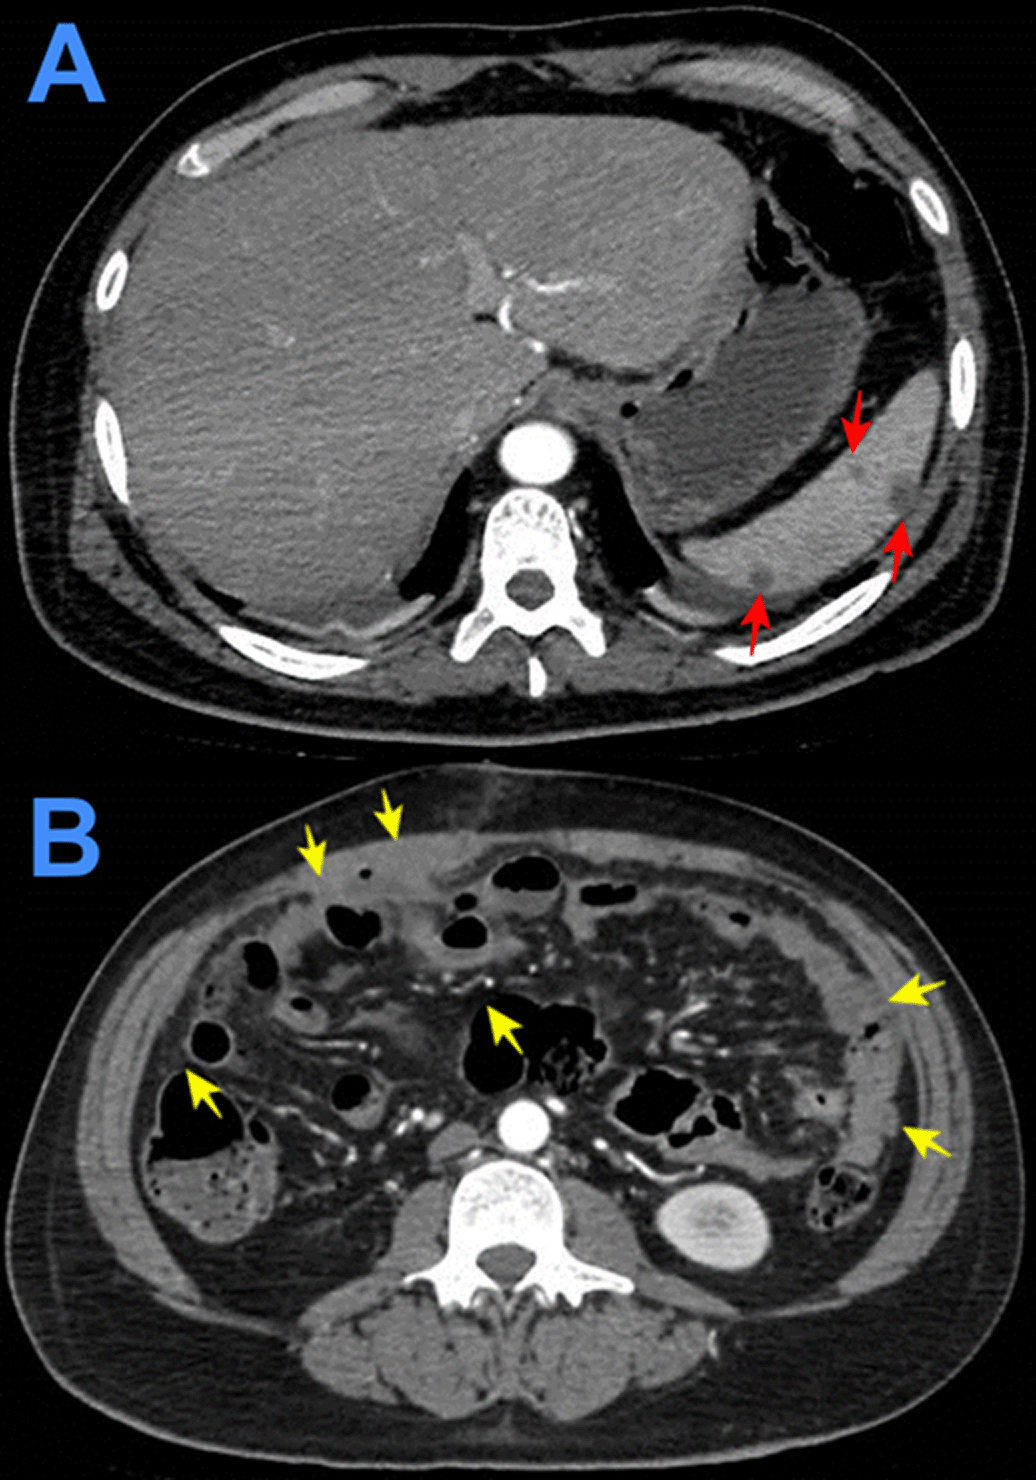

Evolution. One hour after surgery, because of clinical signs of hemodynamic shock, the patient was transferred to the intensive care unit (ICU). At ICU admission the patient was febrile (38.5°C), with hypotension (arterial blood pressure 70/30 mmHg), tachycardia (116 beats per minute), tachypnea (26 breathes per minute) without hypoxia (peripheric saturation 96% in ambient-air), severe dehydration with cold and mottled skin with prolonged capillary refill time, with sleepiness but respondent to verbal stimulus; the abdomen was distended and painful, with reduced intestinal peristalsis, and the wound (8 cm in length) of the recent surgery was macroscopically in order and percutaneous drainages in both iliac fossa were in place showing serohematic secretion. A broad-spectrum antibiotic therapy (meropenem and metronidazole) was started, together with supportive treatment including vasopressors (noradrenaline) and fluid replacement. After a week of the above-mentioned treatment, the clinical condition of the patient was improved and at the seventh day after the surgery, the patient was transferred from the ICU to another hospital division. Then, the result of the histopathological exams of samples collected during surgery showed: “chronic granulomatous inflammation, granulomas, extensive caseous necrosis and Langhans giant multinucleated cells; Ziehl-Neelsen (ZN) stain for Acid Fast Bacilli (AFB) negative”, and a diagnosis of abdominal TB was performed (Figures 1-3). Based on this result quadruple anti-tuberculous treatment (isoniazid 5 mg/kg, rifampicin 10 mg/kg, ethambutol 20 mg/kg, pyrazinamide 25 mg/kg) was initiated in concordance with Peruvian and international guidelines.11,12 Subsequently, the diagnosis was confirmed by a polymerase-chain reaction (PCR) for Mycobacterium tuberculosis in peritoneal fluid. The tuberculin skin test (Mantoux or PPD test) was negative. Serial ZN smears for AFB in urine, sputum, secretion of both pelvic drains, were negative; adenosine deaminase test in peritoneal fluid 292.7 U/L (reference value < 40 U/L). Blood cultures, and cultures for common pathogens, fungi, and M. tuberculosis in urine and peritoneal fluid were negative. Before discharge, the patient was evaluated by an oncologist who suggested some other exams: serum tumor markers (CEA, CA 125, AFP, CA19.9, β-HCG), esophagogastroduodenoscopy, and colonoscopy with ileoscopy, all of which were within normal ranges. In addition, contrast-enhanced chest-abdomen-pelvis computed tomography (CT) and magnetic resonance imaging (MRI) showed “multiple nodular implants in spleen, gut, and peritoneal cavity; but no hepatosplenomegaly or abnormal lymph nodes enlargement” (Figure 4). One week after the start of the antituberculosis treatment, the patient was discharged from hospital because of clinical improvement.

Evolution. After admission, acute abdomen due to appendicitis was diagnosed. Symptomatic treatment was initiated and preoperative exams and plain chest and abdominal x-ray were ordered, which showed significant bilateral pleural effusion and ascites. Three hours after admission, the patient was transferred to the operating room. During exploratory laparotomy “multiple cerebroid nodules scattered through parietal and visceral peritoneum, small bowel, colon and epiploon; and plenty of ascitic fluid were observed”. The postoperative diagnosis was “carcinomatosis”. After surgery, he was transferred to the ICU, and continued treatment with saline, noradrenaline, imipenem, metronidazole, sedation with midazolam, analgesia with fentanyl, and ventilatory support. Based on clinical data, risk factors, intraoperative findings, and chest x ray imaging, TB was suspected. Then, stains and cultures of multiple samples for Mycobacterium tuberculosis (MTB) and a contrast-enhanced tomographic scan of thorax, abdomen and pelvis were ordered (Figure 5). Three days after surgery thoracocentesis was performed. Five days after surgery RT-PCR resulted positive for MTB in pleural fluid and quadruple anti-tuberculous treatment for MTB was initiated (the same scheme as Case 1). Ten days after surgery histopathology of epiploon was obtained, showing extensive caseous necrosis with granulomas and Langhans multinucleated giant cells. The patient died seven days after initiation of anti-tuberculous treatment due to refractory septic shock (Figure 6). A serial ZN smear for AFB in bronchial secretion, blood cultures, and urine culture, were negative. Serologies for HIV, HTLV-1, hepatitis B and C, and RPR/VDRL, were also negative.